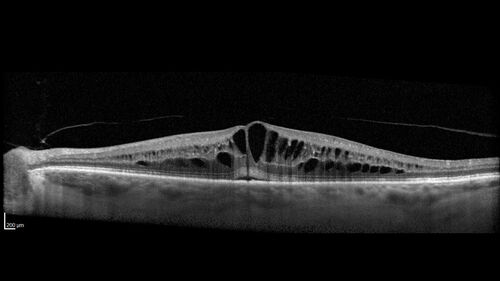

Pseudophakic CME chronic

74 year old man presented 14 weeks after cataract surgery with severe CME on topical therapy.  Multiple attempts to taper drops failed.  Also, the patient had a steroid responsive glaucoma.  He ended up on BID PF, Ketorolac and Dorz/Timolol